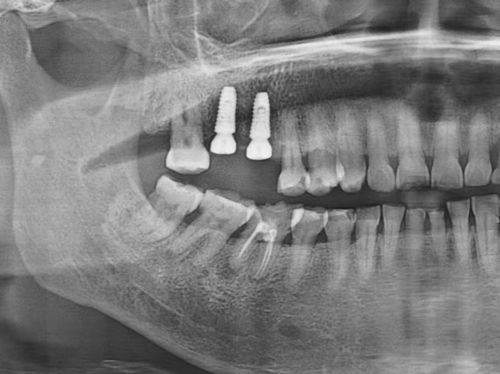

1. 全口和半口种植:高念医生在全口和半口种植方面有着丰富的经验。全口种植是针对牙齿全部缺失的患者,通过植入人工牙根,再安装牙冠,修复患者的咀嚼功能和美观。半口种植则是针对上半口或下半口牙齿缺失的情况。高医生会根据患者的牙槽骨情况、身体状况等因素,选择合适的种植体和种植方案。他会严谨地计算种植体的植入位置和角度,确保种植体的稳定性和成功几率。

2. 不错的技术水平:高医生在全口和半口种植、即刻种植、即刻负重种植以及全口覆盖义齿等方面都有着不错的技术。他能够熟练操作各种精良的口腔设备和仪器,确保手术的精细性和安心性。在种植手术中,他能够严谨地控制种植体的植入位置和角度,提高种植的成功几率。